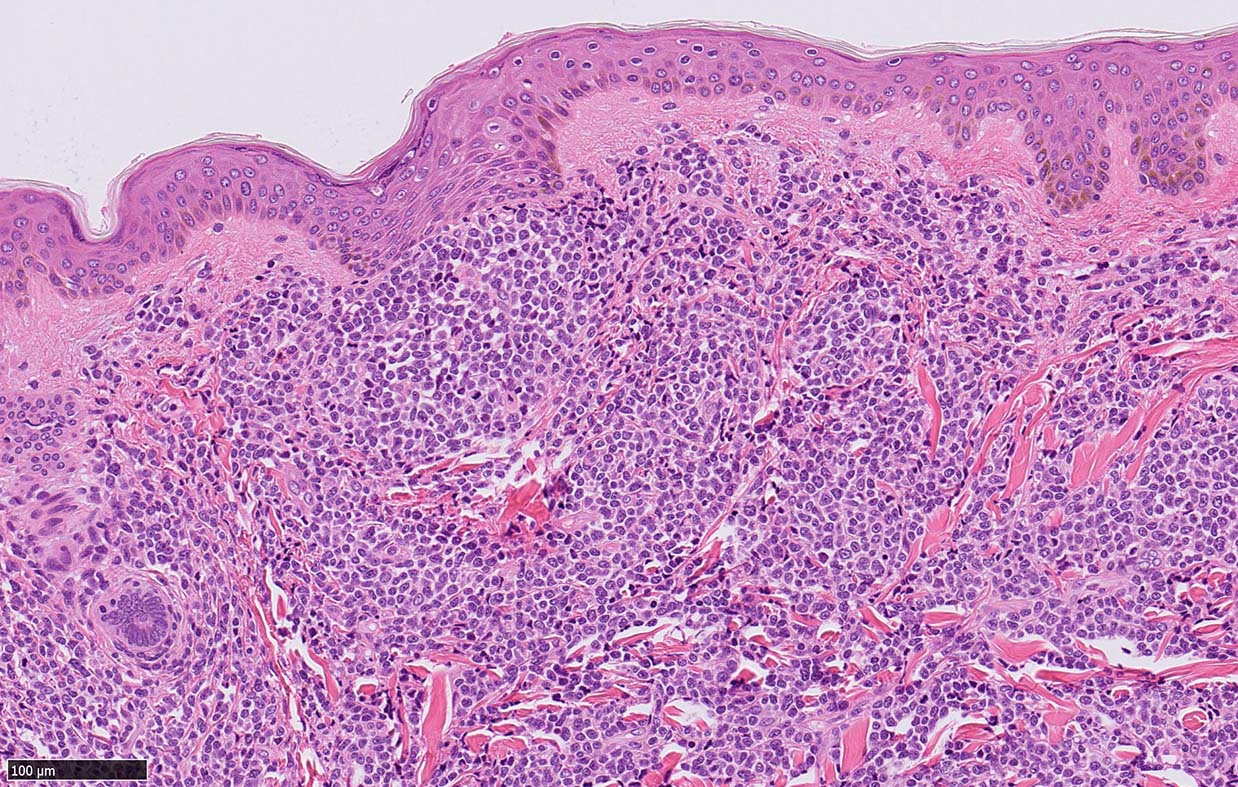

皮膚病変

blasticという名前から「大型細胞」を想起するが, この症例のようなclassical typeの細胞は思ったほど大きくはない. CD123陰性リンパ球とくらべてもあまり大きくないことがわかる.(散在する大型細胞はlysozyme+)

形態は均一で多型はめだたない.

腫瘍細胞は真皮を主座として, 皮下脂肪織まで, びまん性かつ単調monotonousに増殖することが多く, 表皮向性はみられない. 本例では血管や付属器中心あるいは脂肪織内に結節状の浸潤増殖を示した.

BPDCNの増殖細胞形態

BPDCN 腫瘍は形態の異なる2種類の細胞の均一単調な増殖からなる.*4 本例はclassical BPDCNとなる

1. classical BPDCN

腫瘍細胞核は中等大, 不整形. クロマチンは繊細で, 核小体は不明瞭か, 1ないし数個. 細胞は狭小から中程度の量の細胞質をもつ.